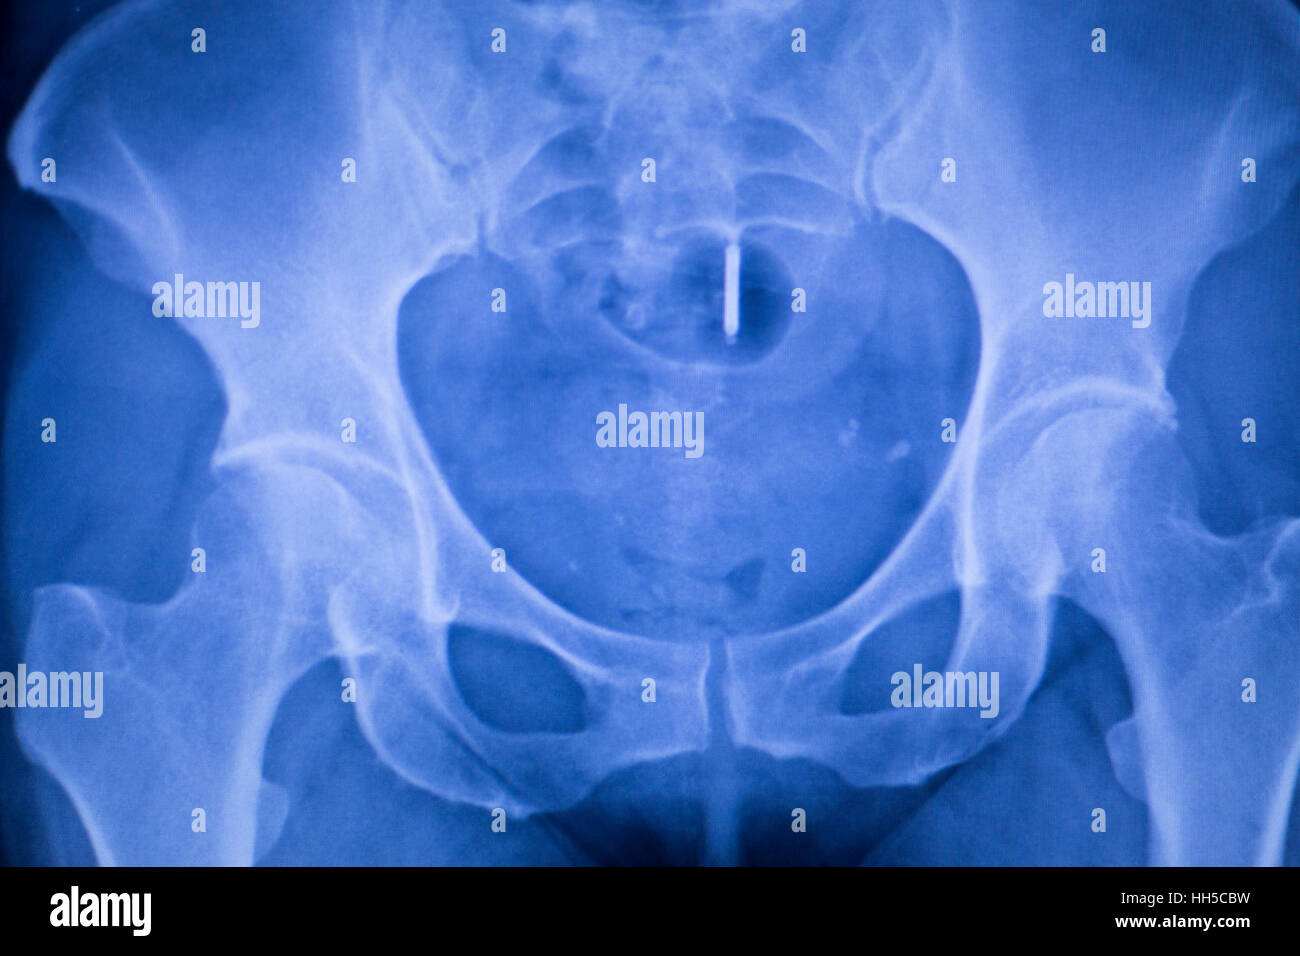

From www.alamy.com

X ray of human hip joint Stock Photo Alamy Hip Joint Catches It is caused by the movement of tendons (the tissue that connects muscles to bones) passing over bone at the hip. Snapping hip syndrome is a snapping sensation that occurs when you walk or stand up. Snapping hip is exactly as it sounds, a snapping sensation around the hip joint with certain motions. The snapping occurs either on the front. Hip Joint Catches.